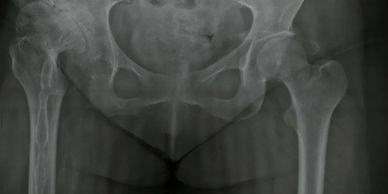

Mirá cómo recuperamos la movilidad en un caso de artrosis severa y deformidad acetabular mediante tecnología 3D de alta precisión. Planificación preoperatoria en 3D para cirugía de cadera con artrosis severa e importante deformidad acetabular. Se imprimieron biomodelos en 3D y guías para la correcta colocación de los componentes protésicos. De esta manera, se logró restaurar la longitud de las piernas y se eliminó el dolor invalidante que presentaba el paciente.

Paciente con artrosis severa y deformidad ósea que dificultaba la colocación acetabular. Con tomografía realizamos planificación 3D y diseñamos una guía quirúrgica personalizada impresa en 3D. En quirófano replicamos el plan: posicionamiento preciso del componente y restauración del centro de rotación. La tecnología 3D aporta más precisión, seguridad y predictibilidad en casos complejos.